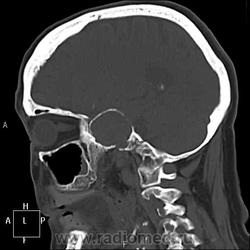

А контраст почему не делали? Больше похоже на тромбированные аневризмы

Неужели такие аневризмы? Бывает же! А сканы с контрастом есть?

Макроаденома гипофиза с интра-эндо-супра-и латероселлярным ростом,инвазией кавернозных синусов и зрительной хиазмы.

В первую очередь подумала бы о менингиоме бугорка турецкого седла или передних наклоненных отростков. Дифференцировала бы с краниофарингиомой но смущает форма.

Да простят моё нахальство уважаемые специалисты КТ. Я вижу тут огромные инкапсулированные узлы расположенные почти симметрично справа и слева от турецкого седла, которое разрушено узлом поменьше. Латеральные злы продавливают дно средней черепной ямы. По-видимому, здесь доброкачественная опухоль типа «аденома», исходящая из гипофиза и давно растущая. Обызвествление есть не только в капсулах узлов, но и в их толще (очаговое). При таких размерах узлов и косных разрушениях, нет сомнения, пострадали и зрительные нервы.

Неоднозначно всё

Цифровых и плёночных доказательств на руках нет. Опухоль диагностирована в 2004 году, размером "с вишню", дебютировала птозом века правого глаза, умеренной головной болью в лобной области слева и постепенным снижением зрения, катаракта. Пациентка с трезвом уме и превосходной памяти (на мой субъективный взгляд))). В выписке результаты КТ, МРТ: неоперабельная опухоль селлярно-параселлярной области с прорастанием кавернозных синусов, аневризма сифона внутренних сонных артерий. Цитологию НЕ брали.

Не совсем понятно, опухоль + аневризма или как?

Да, опухоль, в толще которой аневризма сифона ВСА. Причем с обеих сторон.

Аневризмы с обеих сторон или опухоль?

И то, и другое. Доказать без контрастирования не могу. Когда сама впервые увидела, анамнеза не знала, подумала о двусторонней аневризме. И не угадала.

Насчет опухоли у меня большие сомнения. То что седло растянуто, еще не показатель. Седло увеличивается в размерах даже при гипертонии,а тут такие аневризмы. Самой опухоли не видно, в просвете турецкого седла медиальные полюса аневризм. Ну впрочем не так это важно, интерес чисто теоретический, да и верификации видимо не будет. Спасибо большое за демонстрацию.

Случай-таки не верифицированный. Сочетание опухоли с аневрзмами - это очень странно. Боюсь, тут какая-то путаница.

На мой взгляд, случай требует более внимательного рассмотрения и относительно "готового диагноза", и относительно "неоперабельности".